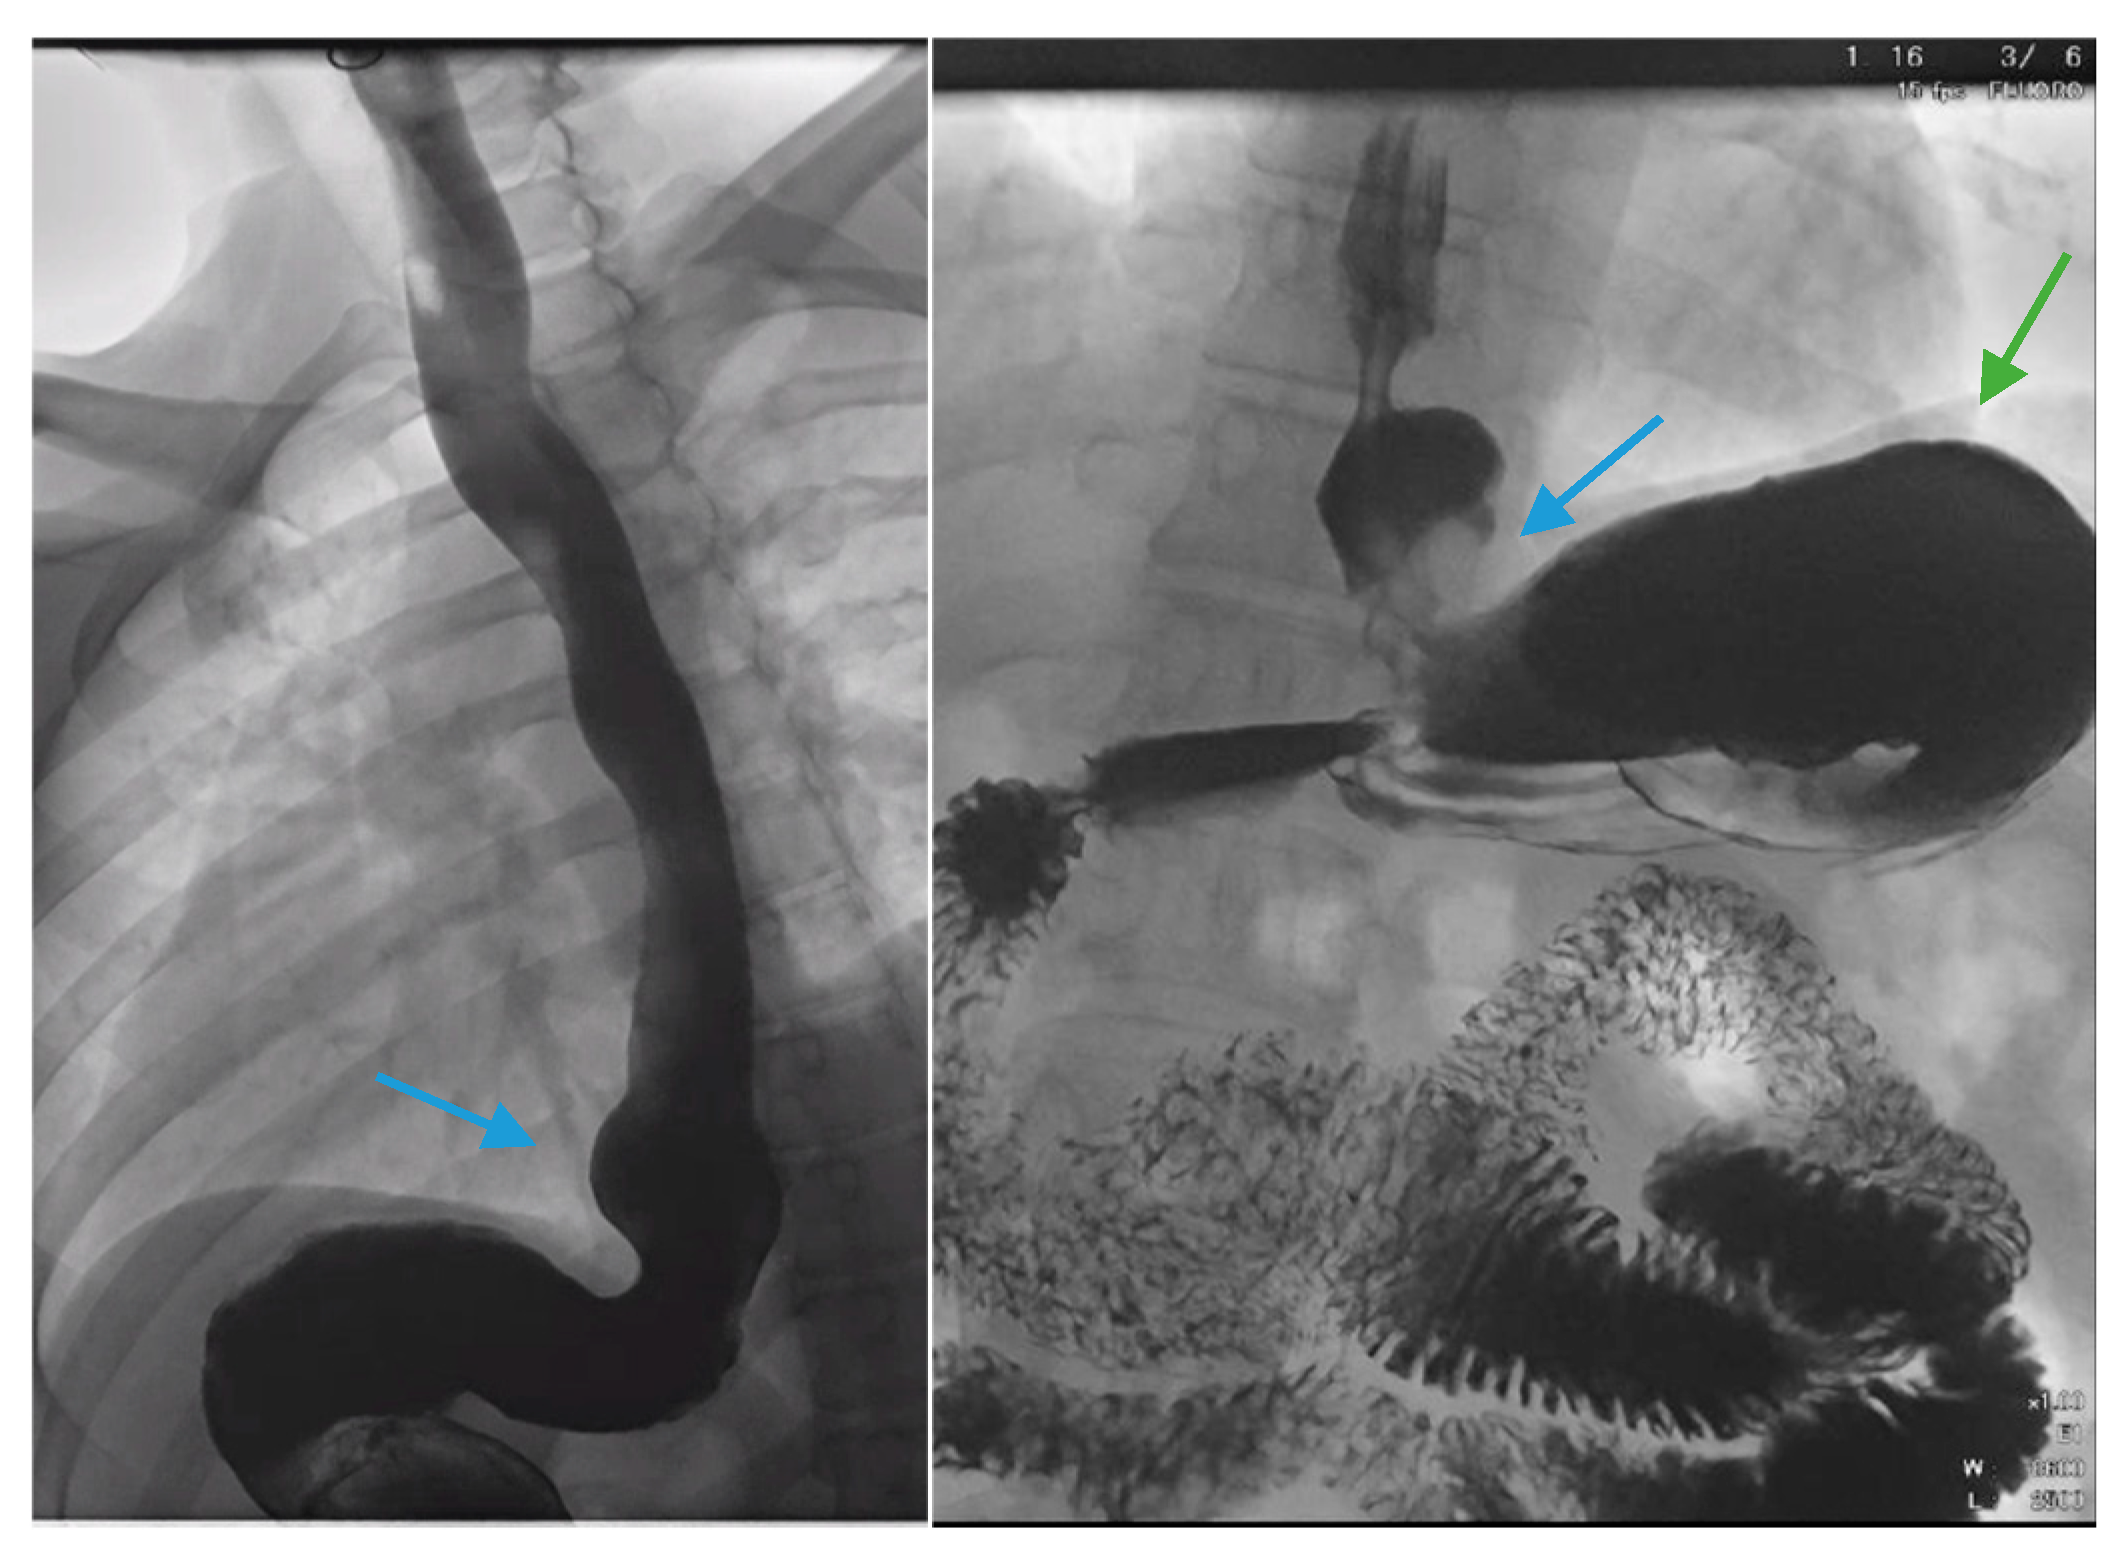

Figure 4. (Left) An upper gastrointestinal series in a patient status post-sleeve gastrectomy with recurrent dysphagia reveals dilation of the gastric sleeve at the cardia (blue arrow) with narrowing and delayed passage of contrast through the middle and distal portions (green arrows) of the gastric sleeve. (Middle) The patient underwent serial endoscopic through-the-scope balloon dilation to 20 mm (blue arrow) with improvement in sleeve stenosis (right) and dysphagia.